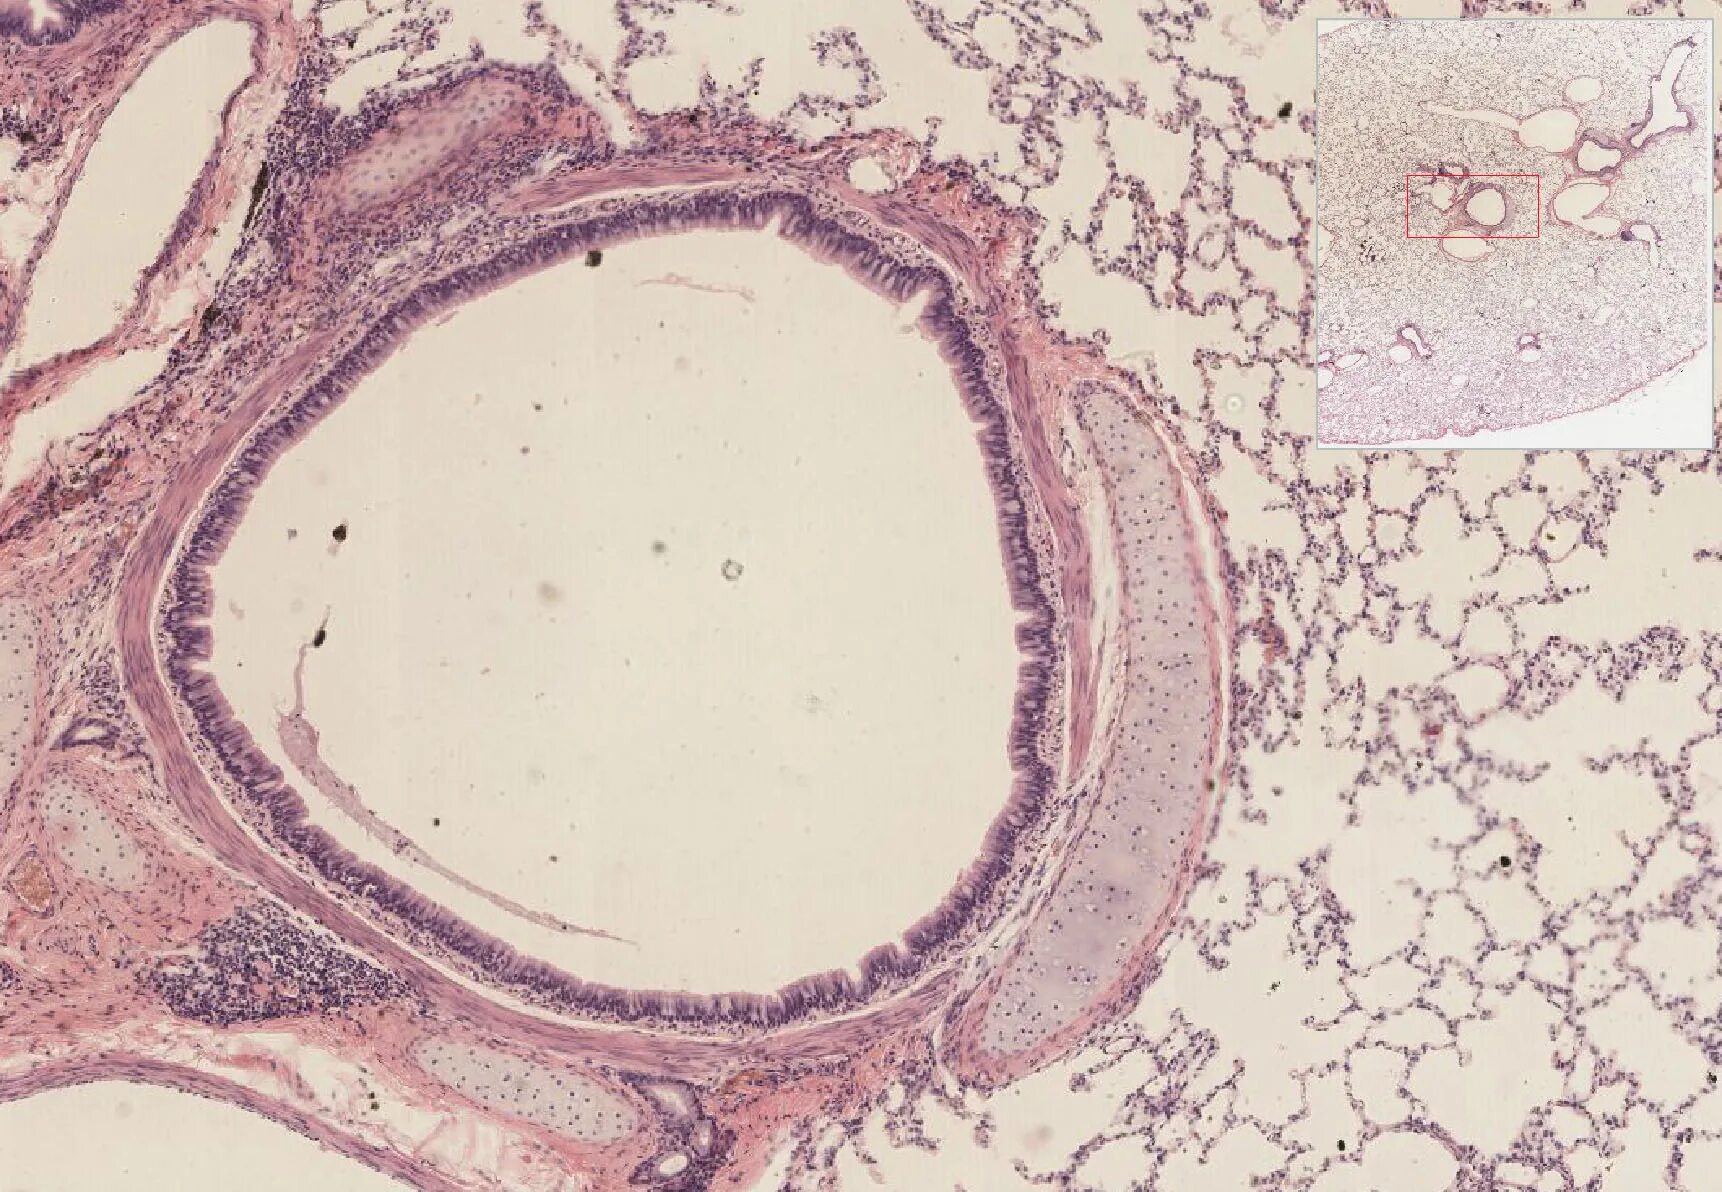

Гистология месяц